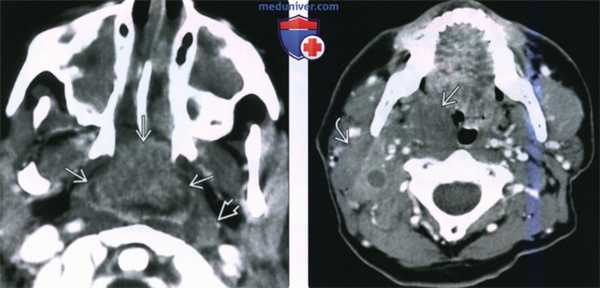

(Слева) При КТ с КУ в аксиальной проекции у ребенка со СПИД в области глоточной миндалины определяется крупная неходжкинская лимфома, неоднородно накапливающая контраст. Обратите внимание на увеличенный лимфоузел в заглоточном пространстве слева и на практически полную обструкцию просвета носоглотки. Полость носа и верхнечелюстные пазухи с обеих сторон заполнены доброкачественным секретом.

(Справа) При КТ с КУ в аксиальной проекции визуализируется мультифокальная неходжкинская лимфома с вовлечением правой небной миндалины, а также группа спаянных лимфоузлов II уровня. Шейная аденопатия встречается в 50% случаев неходжкинских лимфом слизистого окологлоточного пространства.

(Слева) На аксиальной КТ с КУ у ребенка со СПИДом определяется массивная аденоидальная НХЛ с неравномерным накоплением контраста. Обратите внимание на крупный заглоточный лимфоузел слева и практически полную окклюзию просвета носоглотки. Обе верхнечелюстные пазухи и полость носа заполнены секретом (доброкачественные изменения).

(Справа) На аксиальной КТ с КУ определяется мультифокальная НХЛ с вовлечением миндалины справа и лимфоузла II уровня с экстранодальным распространением. Шейная лимфаденопатия присутствует более чем в 50% случаев НХЛ слизистой оболочки глотки (СОГ).